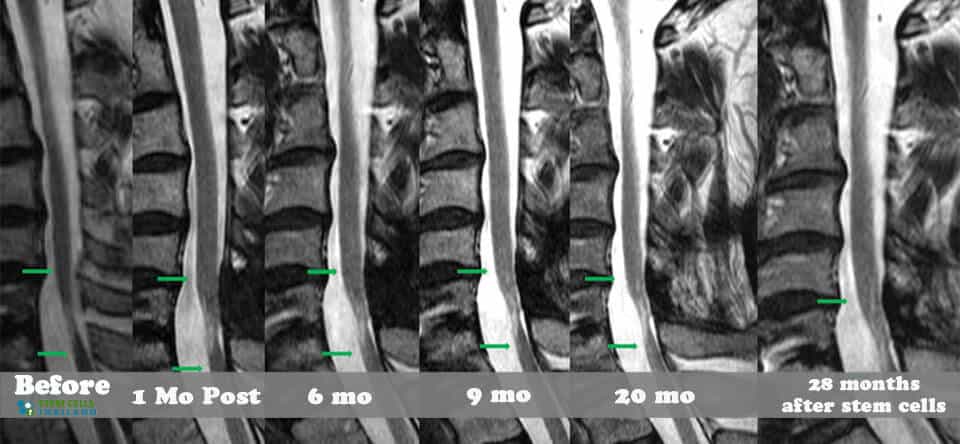

脊髓損傷的干細胞治療

脊髓損傷的細胞療法側重于大腦和身體之間軸突的再生,這些軸突在事故發生后受到嚴重限制或不存在。我們針對脊髓損傷的干細胞移植可以幫助患者消除疼痛,恢復膀胱和腸道功能,恢復失去的感覺,并再生內臟運動神經元,同時最大限度地減少其他問題,例如損傷引起的痙攣或抑郁。傳統治療不解決再生問題,而是側重于疼痛管理、康復和減少繼發性損傷。

基于細胞的治療采取更積極主動的方法,通過刺激/增強受損細胞和組織的修復來促進人類的自然修復周期。修復受傷的脊髓和竹脊柱需要超越任何傳統技術來幫助您恢復部分/全部失去的功能。臨床試驗表明,細胞更新和死亡是非常正常的,當身體細胞受傷或老化時,細胞會自然發生。這些死亡細胞通常被健康和受損的細胞包圍。我們針對坐骨神經痛和椎管狹窄的治療方案通過利用神經生長因子和旁分泌信號傳導的靶向細胞因子療法,有助于促進這些死亡或受傷細胞的愈合欺騙身體重新開始愈合過程。

對于具有廣泛神經細胞萎縮的嚴重病例,治療需要通過CT引導的脊柱內機器將擴增的MSC+間充質干細胞和神經細胞生長因子注射到受損的脊柱區域附近。針對脊髓損傷的MSC+方案是獨一無二的,因為它是世界上唯一提供補充注射神經細胞特異性生長因子的治療方法,根據損傷的嚴重程度,使用腰椎穿刺、鞘內注射或靜脈滴注進一步促進康復。

脊髓損傷修復

增強型MSC+干細胞注射是現代再生醫學的白金標準,尤其是在處理脊髓橫斷時。細胞引導的精確性使我們的團隊能夠直接瞄準鄰近的病變或損傷區域。MSC+增強型脊柱治療不需要危險的開放性脊柱手術。MSC+干細胞注射和神經祖細胞輸注還可以幫助患者避免與傳統治療脊髓損傷相關的額外手術的風險和痛苦。[1]

我們脊柱損傷治療中心的目標是幫助以自然和安全的方式修復損傷。我們的治療是在細胞水平上進行的,僅影響靠近影響點的區域。如果受傷時間不到兩年,積極的結果可能會非常顯著。對于那些患有老年損傷、創傷性腦損傷、嚴重椎間盤退變、股骨頭壞死、周圍神經病變或脊髓性肌肉萎縮的人來說,隨著時間的推移,完全康復的機會變得更加困難。

組織、軟骨或韌帶的新損傷對干細胞治療的反應要好得多。治療后的康復需要大量的奉獻和康復訓練。初次治療后約2-3個月,身體改善明顯,且效果是永久性的。[2]